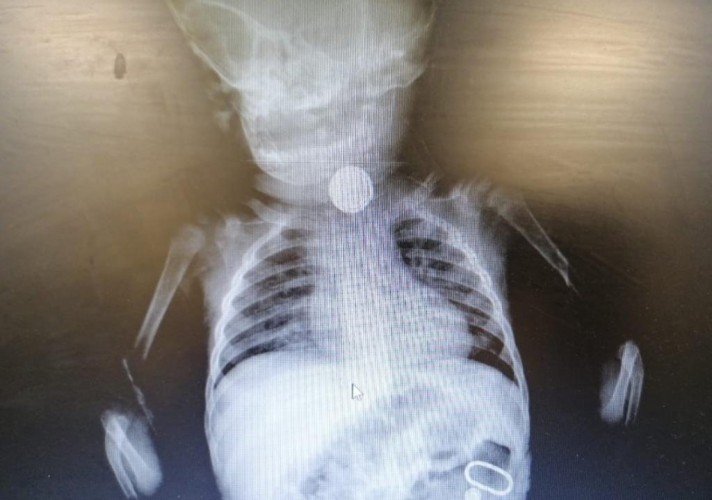

أسهم – بفضل الله – فريق طبي متخصص في مستشفى القريات العام في إنهاء معاناة رضيع يبلغ من العمر 10 أشهر، بعد استخراج جسم غريب من أعلى المريء ،حيث تبين بعد إجراء التحاليل والأشعة اللازمة وجود بطارية ساعة،مما استدعى اتخاذ قرار بالتدخل واستخراجها بواسطة المنظار، ويتمتع الطفل بحالة صحية جيدة ولله الحمد.